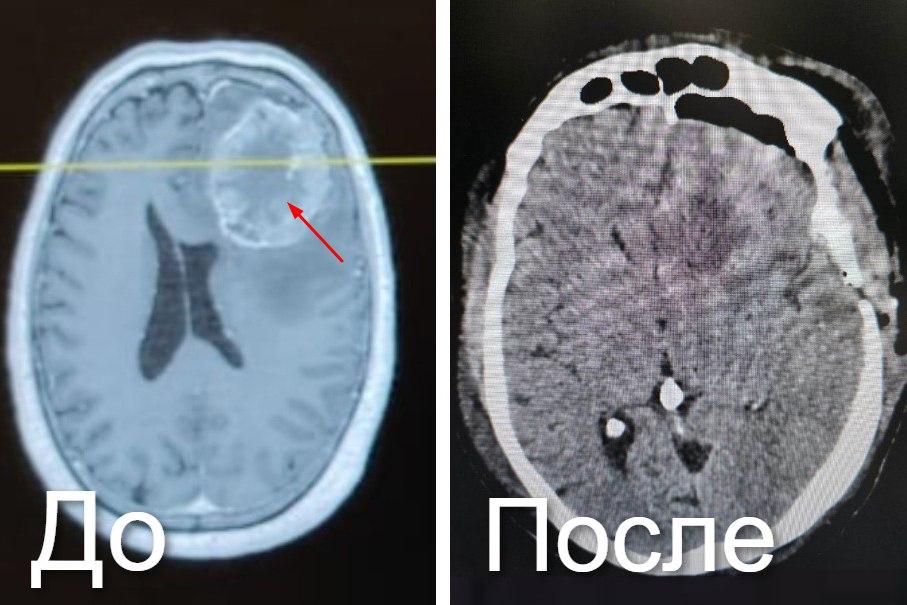

«Ювелирную» операцию под микроскопом на мозге провели хирурги в Новокузнецке

Опухоль, размером 7,6 на 6 см, возникла после рака прямой кишки, пациент 6 лет не наблюдался у онкологов. Спровоцировала сильную боль, потерю координации и тошноту. Новообразование с нечеткими границами удалили под микроскопом и контролем нейронавигационной системы.